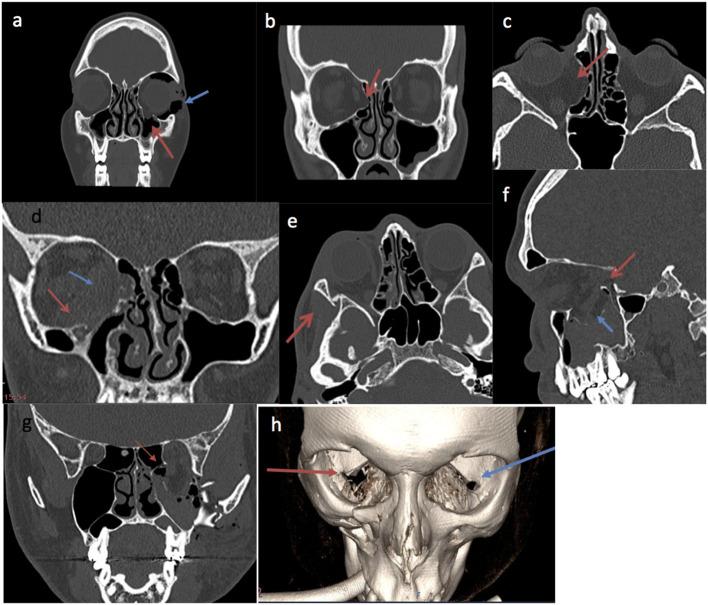

The decision for open reduction and internal fixation (ORIF) of orbital fractures is usually based on clinical severity and soft tissue and bony findings. This study aimed to identify prognostic factors for a successful surgical outcome. We included all orbital fractures treated by ORIF referred to the Ophthalmology clinic for assessment over a 12-year period. A successful outcome was defined as (i) a single operation, (ii) improved diplopia and globe position at 6 months, (iii) no surgical complications, and (iv) patient satisfaction. Data was collected on presenting symptoms, orthoptic measurements, time interval from injury to surgery, fracture geometry and involvement of internal, and external bony landmarks. Univariate and multivariate regression was used to identify predictive factors for success. There were 143 cases with median age 35.4 years and 81.8% (117/143) male. 51% (73/143) were complex fractures involving multiple orbital walls. 63.6% (91/143) achieved significant improvement in both enophthalmos and diplopia at 6 months. 15.3% (22/143) had significant preoperative soft tissue or neurogenic injury. 11.8% (17/143) required orbital plate repositioning or removal. 1.4% (2/143) developed orbital haematoma and 4.2% (6/143) had cicatricial entropion. Pre-operative nerve or muscle damage (OR 0.05, = 0.01) and infraorbital fissure fracture (OR 0.38, = 0.04) were associated with poor outcomes, whereas an intact posterior ledge was associated with successful outcomes (OR 3.03, = 0.02). Careful ocular motility evaluation to ascertain neurogenic injury and muscle compartment syndrome, and radiological analysis of the integrity of the posterior ledge and the inferior orbital fissure can facilitate management and expectations of ORIF surgery.

眼眶骨折切开复位内固定术(ORIF)的决策通常基于临床严重程度以及软组织和骨质情况。本研究旨在确定手术成功的预后因素。我们纳入了在12年期间转诊至眼科诊所接受评估的所有接受ORIF治疗的眼眶骨折患者。成功的结果定义为:(i)单次手术;(ii)6个月时复视和眼球位置改善;(iii)无手术并发症;(iv)患者满意。收集了关于就诊症状、斜视测量、受伤至手术的时间间隔、骨折形态以及内外侧骨性标志受累情况的数据。采用单因素和多因素回归分析来确定成功的预测因素。共有143例患者,中位年龄35.4岁,81.8%(117/143)为男性。51%(73/143)为累及多个眶壁的复杂骨折。63.6%(91/143)在6个月时眼球内陷和复视均有显著改善。15.3%(22/143)术前存在明显的软组织或神经源性损伤。11.8%(17/143)需要重新定位或取出眶板。1.4%(2/143)发生眶内血肿,4.2%(6/143)出现瘢痕性睑内翻。术前神经或肌肉损伤(OR 0.05,P = 0.01)和眶下裂骨折(OR 0.38,P = 0.04)与不良预后相关,而后壁完整与成功预后相关(OR 3.03,P = 0.02)。仔细的眼球运动评估以确定神经源性损伤和肌间隔综合征,以及对后壁和眶下裂完整性的影像学分析,有助于眼眶骨折切开复位内固定术的管理和预后预期。